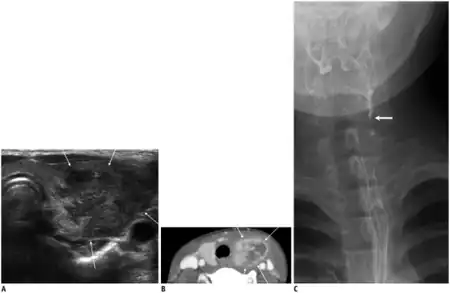

Patients who are suspected of having AIT often undergo tests to detect for elevated levels of white blood cells as well as an ultrasound to reveal unilobular swelling.[1][4] Depending on the age and immune status of the patient more invasive procedures may be performed such as fine needle aspiration of the neck mass to facilitate a diagnosis.[4] In cases where the infection is thought to be associated with a sinus fistula it is often necessary to confirm the presence of the fistula through surgery or laryngoscopic examination.[6] While invasive procedures can often tell definitively whether or not a fistula is present, new studies are working on the use of computed tomography as a useful method to visualize and detect the presence of a sinus fistula.[6]